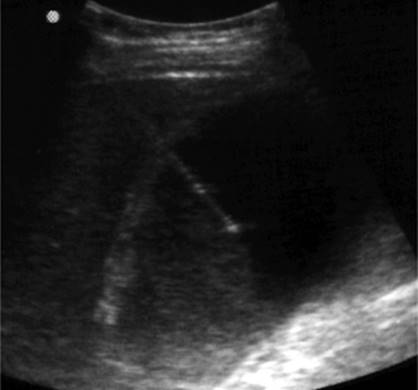

Figure 35.6. Ultrasound image showing typical appearance for thoracentesis guidance. The central target (pleural effusion) is identified by an asterisk, lung margin by arrowheads, and drainage catheter pathway with an arrow.